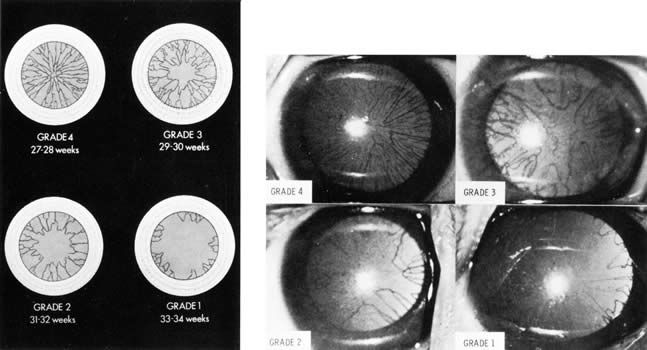

Involution of the anterior portion of the tunica vasculosa lentis (pupillary membrane) occurs predictably with gestational age.199 Direct ophthalmoscopic examination of the pupillary membrane within the first 24 to 48 hours of life, aided by dilating the pupil, allows an arbitrary grading that is highly correlated with gestational age (Fig. 9). This assessment is also valid for most infants who are small for gestational age (SGA).200 Its value in multiple pregnancy has been questioned.201 Abnormal persistence of the pupillary membrane and asymmetry between the eyes occur with congenital toxoplasmosis, rubella, cytomegalovirus, and herpes simplex infection.202

Fig. 9. Grading system for assessment of gestational age by examination of the anterior vascular capsule of the lens. (Used with permission from: Hittner HM, Hirsch NJ, Rudolph AJ: Assessment of gestational age by examination of the anterior vascular capsule of the lens. J Pediatr 91:455, 1977.)